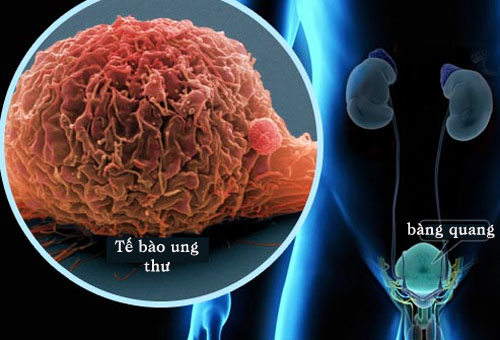

Hình ảnh tế bào ung thư

Dấu hiệu cảnh báo nguy cơ ung thư bàng quang

Những thay đổi ở bàng quang có thể là dấu hiệu cảnh báo ung thư bàng quang